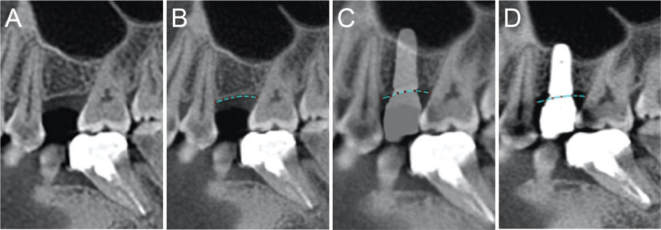

Purpose: To investigate the correlation between the marginal bone height of implants in the posterior maxilla of patients with periodontal disease and the inclination of cusp, providing a theoretical basis for the occlusal design of implant restorations in such patients.  Methods: A total of 80 patients with periodontal disease who underwent implant restoration in the posterior maxilla (55 men and 25 women; mean age 56.66 ± 12.70 years) were selected, with a total of 80 implant restorations (one implant restoration per patient). In addition to recording the main research factor of the inclination of cusp, general patient information, implant characteristics and restoration characteristics were taken, and retrospective analysis of the case data and imaging data of the 80 patients from over 3 years was conducted. Cone beam computed tomography was performed preoperatively and 3 years after implant loading to measure and calculate the marginal bone height of the implants using the One Volume Viewer software. Correlation analysis was performed to determine the relationship between the inclination of the cusp and marginal bone height.  Results: There was a positive correlation between the inclination of cusp and the marginal bone height of the implants, with a correlation coefficient of 0.661 (p < 0.001); the diameter of the implants, implant type and restoration type were negatively correlated with the marginal bone height of the implants, with correlation coefficients of -0.364 (p = 0.001), -0.232 (p = 0.038) and -0.298 (p = 0.007), respectively.  Conclusion: When designing the occlusion of implant restorations in the posterior maxilla of patients with periodontal disease, it is advisable to appropriately reduce the restoration's inclination of cusp.